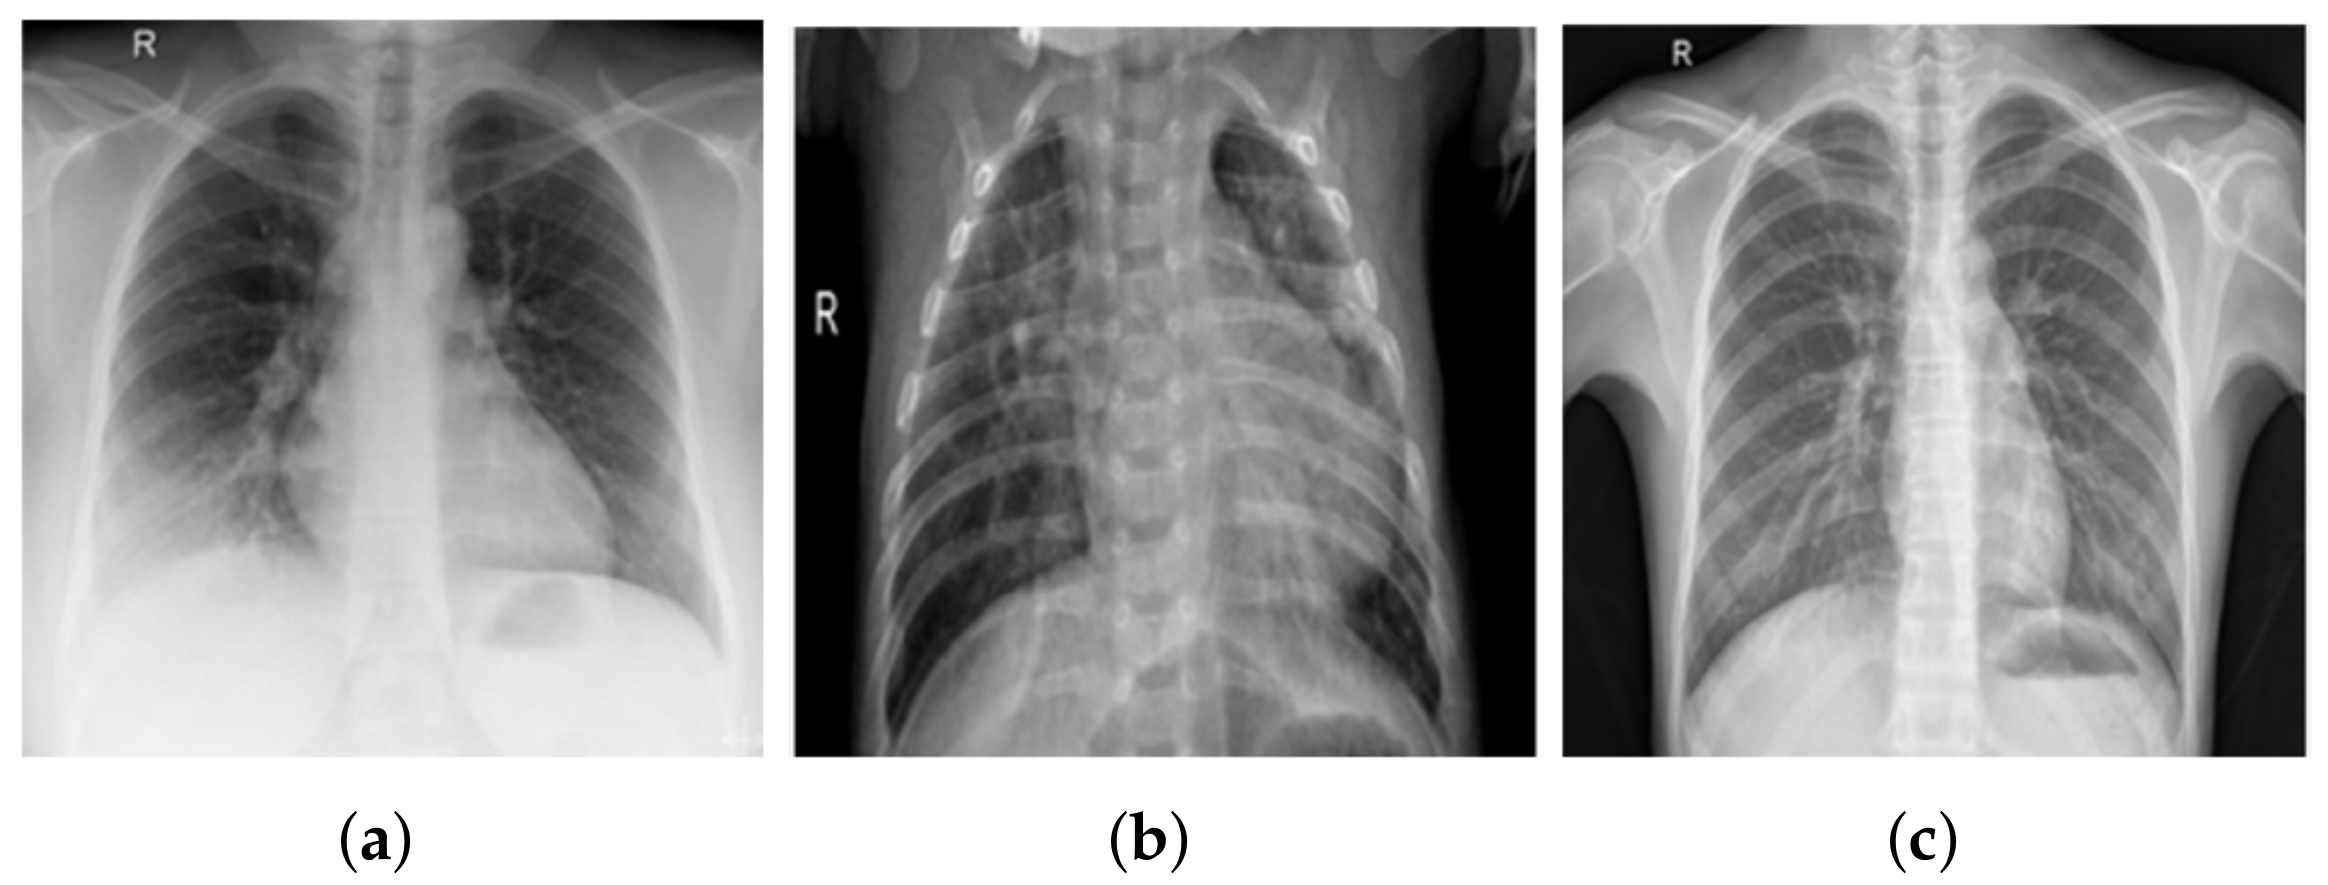

3.1. COV-PEN Image Datasets